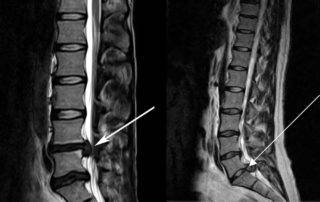

Миелография с контрастом — видны поврежденные участки

- Миело(томо)графия. Контрастное вещество вводят в субарахноидальное пространство для визуализации спинного мозга и определения проходимости.